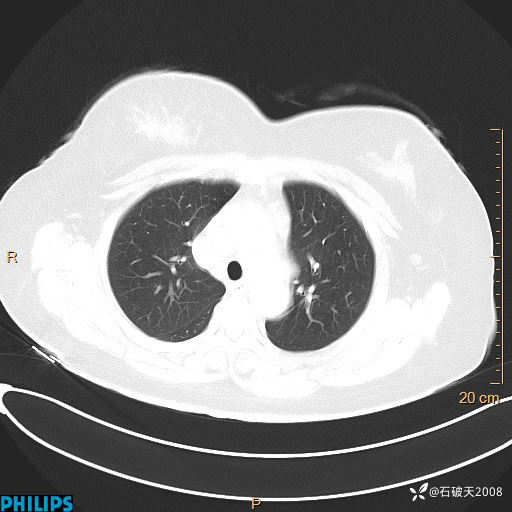

肺结节病?纵膈型肺癌?淋巴瘤?有点意思,欢迎围观

女 52岁 主 诉:咳嗽10余天,咳痰2天。

现病史:10余天前无明显诱因出现咳嗽,呈阵发性干咳,伴咽喉部发痒,无咽痛,无咳痰,无鼻塞、流涕、打喷嚏,无发热、畏寒、寒颤,无头痛、头晕,无胸闷、胸痛,无反酸、烧心,无腹痛、腹泻,无尿频、尿急,无皮疹等,在当地诊所求治,给予口服药物治疗(具体不详),病情无好转。遂在当地社区卫生服务中心开具口服药物治疗(具体不详),疗效欠佳。2天前出现咳痰,在我院门诊求治,行胸部CT提示肺部感染,建议住院,患者要求口服药物治疗,目前仍咳嗽、咳白色粘痰,白天量多,夜间自觉喉部喘鸣音,遂再次来院就诊,以“肺部感染”为诊断收入院。发病以来,神志清,精神可,饮食可,夜间睡眠差,大小便正常,近期体重无明显变化。

纵隔窗